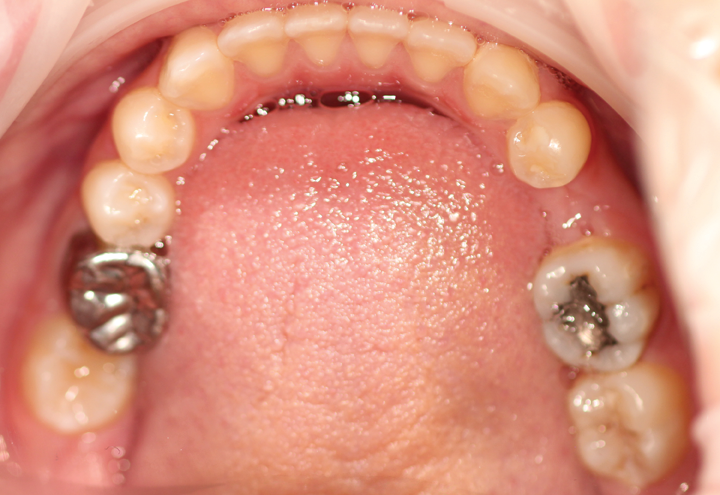

Then, I captured an STL scan (Fig. 6) using PlanScan (E4D), an open source scanner that produces a vector file composed of thousands of tiny triangles that map out the 3D shape of the scanned area. Because i-CAT is also an open source, I am able to use both of these scans together in many third-party planning software programs. For this case, I used BlueSky Plan® to virtually and precisely place the implant (Figs. 7 and 8). I decided on the use of an OCO Biomedical 4 mm x 12 mm TSI implant with the guided implant kit.

Fig. 7 Fig. 8

When I finished my planning, I packaged up the scan files and plan and sent them to Digi3Dworks for the fabrication of the surgical guide. The CBCT and STL information create very accurate data from which the surgical guide could be printed by the lab. I had the surgical guide back in my office in a week.